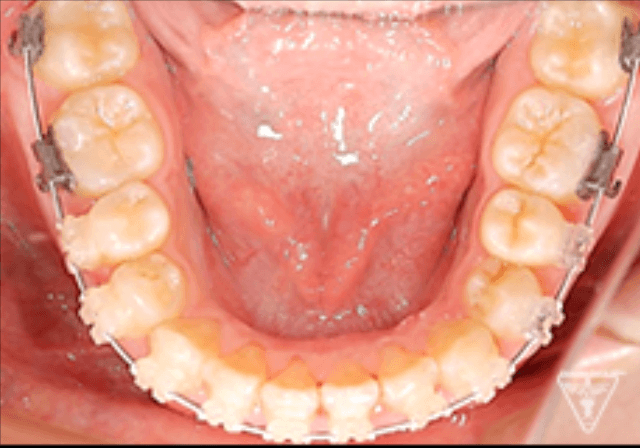

矯正器具 装着時の治療過程

後期